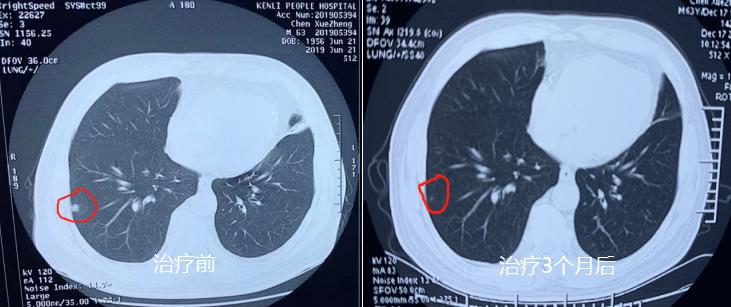

2019年李先生突然断断续续的咳嗽了起来,以为咽喉炎犯了,但吃了药也不管事儿,而且这一咳就是3个多月,也不见消停。后于2019年6月21日李先生在其家人的陪伴下到医院检查,结果发现:右肺叶及下叶见结节影,较大者直径约为7mm,边缘光滑,左肺纤维灶,主动脉及冠状动脉粥样硬化,脂肪肝。医生建议继续观察,定期随访。

6月21检查

2019年9月18日李先生去医院复查:发现双肺多发微小结节,右肺下叶结节较之前变大,直径约10mm,脑内多发缺血灶,脑动脉及冠状动脉粥样硬化并多动脉狭窄,甲状腺两侧叶结节样病灶,甲状腺右侧叶中部1*0.7cm,甲状腺左侧叶下部结节1.5*1.1cm(3级)。

9月18日复查

9月18复查

经3个月的中医调方治疗,患者身体状况不断改善。2019年12月17日患者上当地医院复查,提示结节明显缩小。当时为其做检查的医生通过电脑测得患者的结节已缩小至0.1cm。患者感慨幸好当时坚持不手术,沉重的心情也豁然开朗了,对接下来的治疗也更有信心。目前该患者仍在服用中药继续巩固治疗当中。

治疗前和治疗后对比

治疗三个月复查,结节明显缩小